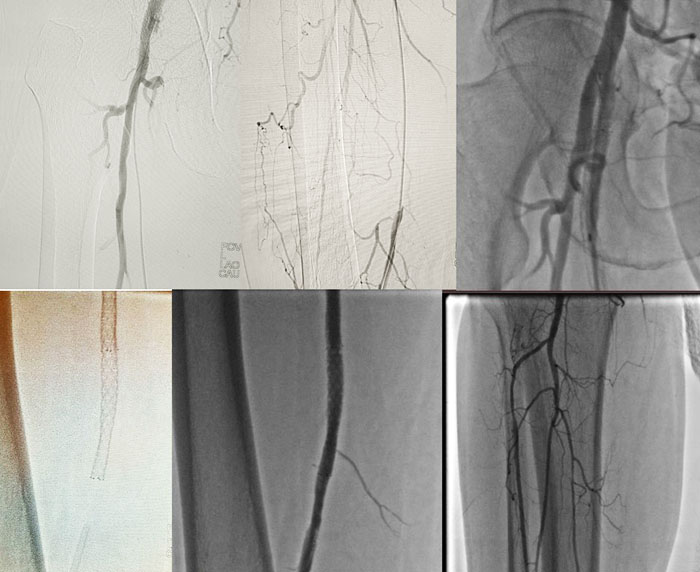

Arterial rekonstruksiyaların nəticələri

Radiotezlikli obliterasiyaların nəticələri

Skleroterapiyaların nəticələri